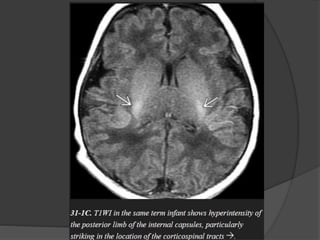

Maple Syrup Urine Disease

Symptoms usually develop within a few days after birth and

include poor feeding, lethargy, vomiting, and seizures.

In severe cases, the urine smells like maple syrup or burnt

sugar.

NECT scans

show profound hypodensity in the myelinated WM with

vasogenic edema in the (Areas of early myelination) dorsal

brainstem, cerebellum, cerebral peduncles, and posterior limb

of the internal capsule.

MR scans show striking T2/FLAIR hyperintensity with relatively

crisp margins.

DWI shows restricted diffusivity